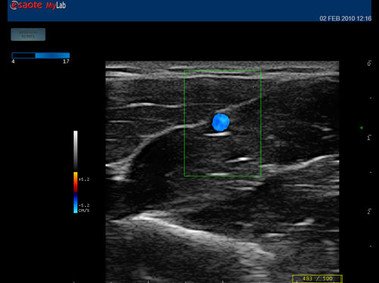

• Features: Farb/Doppler, Nadelführung, SW/B-Bild

Welches Baujahr ist das Esaote MyLabOne?2009 In welchem Zustand war das Esaote MyLabOne, als Sie es gekauft haben?Refurbished Welche Ultraschallverfahren nutzen Sie mit dem Esaote MyLabOne? 2D, Duplex Wie würden Sie die Bildqualität des Esaote MyLabOne bewerten? Sehr gute detailreiche Auflösung und Kontrast Wie bewerten Sie das Preis-Leistungsverhältnis des Esaote MyLabOne bewerten? Kein Fehlkauf Bitte beschreiben Sie in einem Satz, Ihre Erfahrungen mit dem Esaote MyLabOne. Sehr gutes High-End Gerät. Bei wem haben Sie Ihr Esaote MyLabOne gekauft? Esaote Hersteller Wie viel haben Sie damals für das Esaote MyLabOn ein Euro gezahlt? (Bitte geben Sie den Wert ohne Punkt und Komma an) 4000€ Beinhaltet der Kaufpreis einen Servicevertrag?Nein